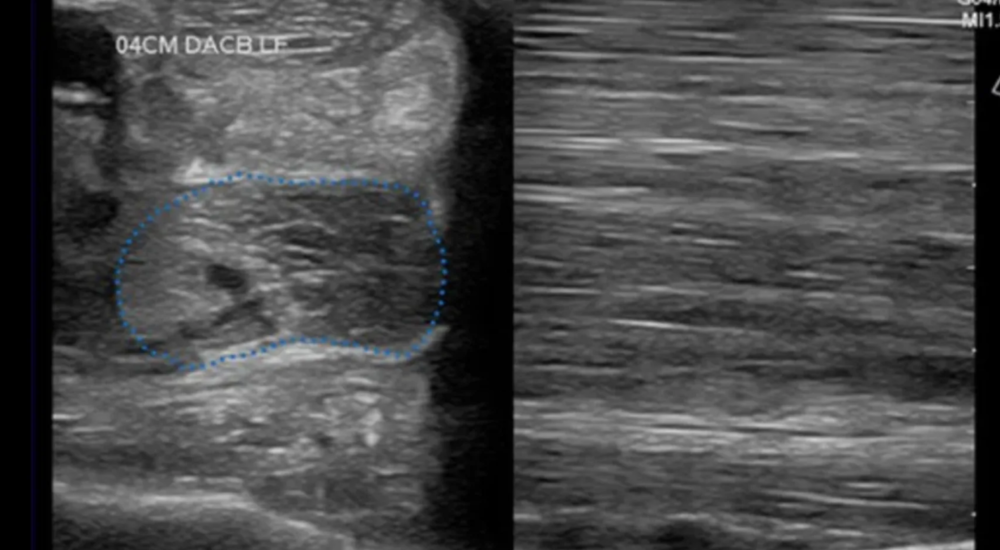

Horse landed badly from jump and became acutely lame. On initial presentation, horse had severe swelling in the flexor tendon region.

Ultrasound examination confirmed tendonitis of the SDF. Small multifocal tears and diffuse hypoechogenicity was visualized in approximately 2/3 of the tendon’s length in the metacarpal region.

Initial treatment included icing, anti-inflammatories, bandaging, and wedge pads taped to the foot to help elevate the heel.

Platelet-rich plasma was also infused into the lesion under ultrasound guidance.

Current Status: 3 months post-injury-Horse is sound at the walk and is being tack-walked.